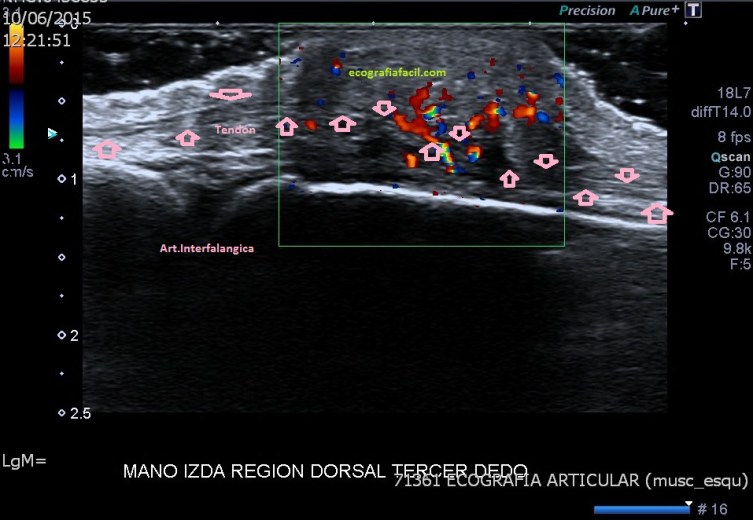

Quiero que te fijes en la imagen 4 y busques y sigas el tendón extensor del dedo, muy fino, observa como se puede seguir su recorrido a lo largo de la lesión producida por el acúmulo gotoso, en la imagen 5 te lo marco con flechas rosas para que te sea más fácil.

Se explora ecográficamente con sonda de alta resolución la región dorsal del tercer dedo de la mano izquierda, a la altura de la articulación metacarpofalángica.

Se diagnostica de Tofo Gotoso, al contrario que el tumor de células gigantes, que es normalmente homogéneo, este es heterogéneo. Como he dicho, el diagnóstico diferencial es tumor de células gigantes por la localización, pero el dato que da el diagnóstico en esta exploración es este: Hiperuricemia crónica de larga evolución en tratamiento (Gota). La historia clínica del paciente corroboran el diagnóstico.